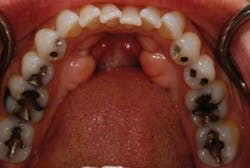

Full arch, occlusal images, as part of a photographic series, are an important adjunct to the new-patient examination. Images of only one or two teeth, such as those commonly captured with an intraoral camera, center on single-tooth dentistry but do little to help clinicians, staff, or patients think about patient needs in a comprehensive fashion (Fig. 1). The way clinicians evaluate and communicate with patients should be in alignment with the way they wish to treat their patients. Patients can better understand their needs when they can clearly see the "big picture." Full arch, occlusal images are an excellent way to help patients see the big picture and should be part of any new-patient examination (Figs. 2 and 3).